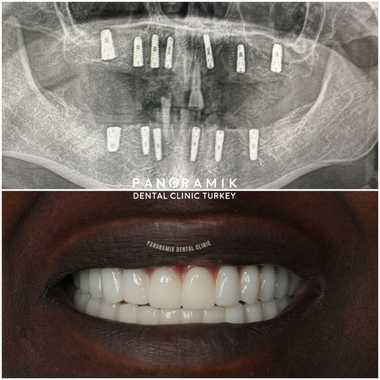

Image-1: Full mouth implants

In the treatment of fixed implant or complete edentulism, the first examination is performed by your dentist. Then it is decided how many implants will be placed. At least 5 implants are placed, but this number varies according to the patient's systemic condition and bone level. The type of prosthesis is determined according to the number of implants. While 2-4 implants are used for removable prostheses, 5 or more implants should be placed for fixed prostheses.

In implant application in complete edentulism, fixed or removable prosthesis is made on the implant. These implant-supported prostheses provide our patients with psychological support and self-confidence as well as ease of use.

- It provides an aesthetically natural appearance.

Smile Time: Your smile will last for years with your teeth that have been used carefully and carefully and whose controls have not been interrupted. Take a look at our Before and after pictures.